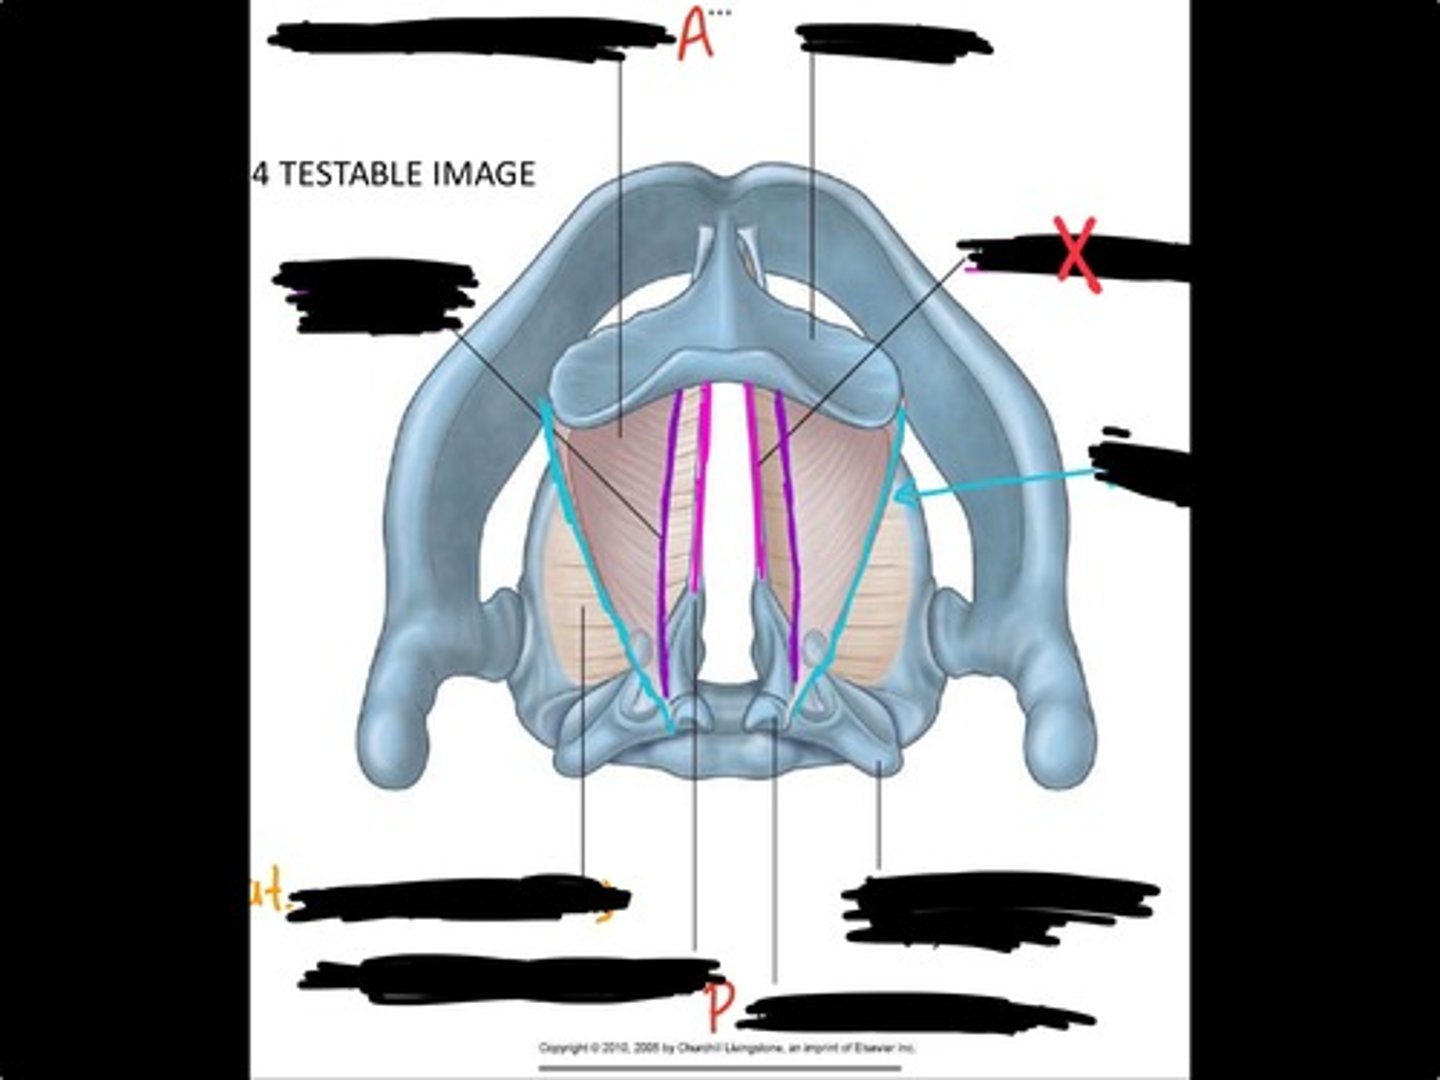

Vocal process of arytenoid

Conus elasticus

Vestibular ligament

Quadrangular membrane

Epiglottis

vocal ligament

Aryepiglottic ligament

Muscular process of arytenoid

Corniculate cartilage

Posterior crico arytenoid

oblique arytenoid

transverse artyenoid

Rima glottidis

Vocal ligament

Vocalis muscle

Lateral cricothyroid ligament

Lateral cricoartenoid